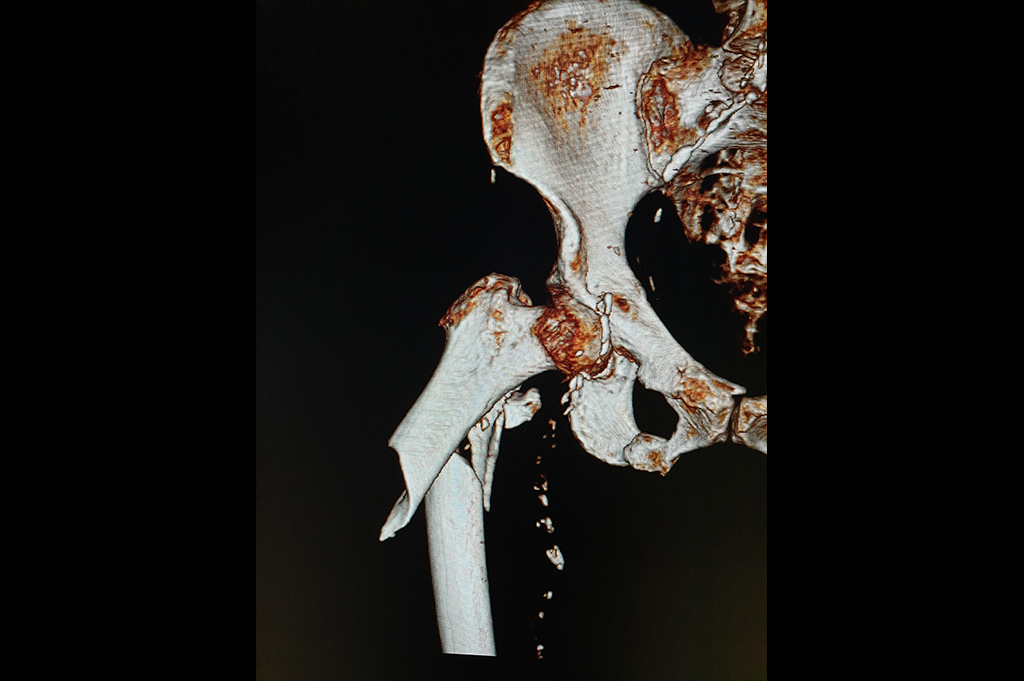

Neck Femur Fracture